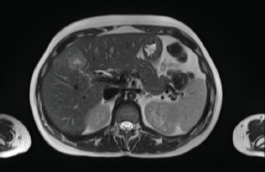

In 2018, a 33-year-old patient, Gravida 3, Caesarean 2, was evaluated in the 16th week of pregnancy. During the physical examination, tumour was palpated in the retroareolar region. This tumour was of increased consistency, with a maximum diameter of approximately 10 cm, irregular margins and clinically negative axilla. Needle biopsy: infiltrating ductal carcinoma, histological grade 3. Immunohistochemistry results: oestrogen receptor-positive (35%), progesterone receptor-positive (85%), HER2/neu-positive (Score 3+), Ki67 = 37%. Whole-body nuclear magnetic resonance without contrast found images consistent with hepatic metastasis of segment V measuring 29 mm (Figure 1) and millimetric metastases in the right iliac bone. Genetic test was negative (BRCA 1 and 2 not mutated).

Figure 1. Whole-body nuclear magnetic resonance without contrast: images consistent with hepatic metastasis of segment V measuring 29 mm.